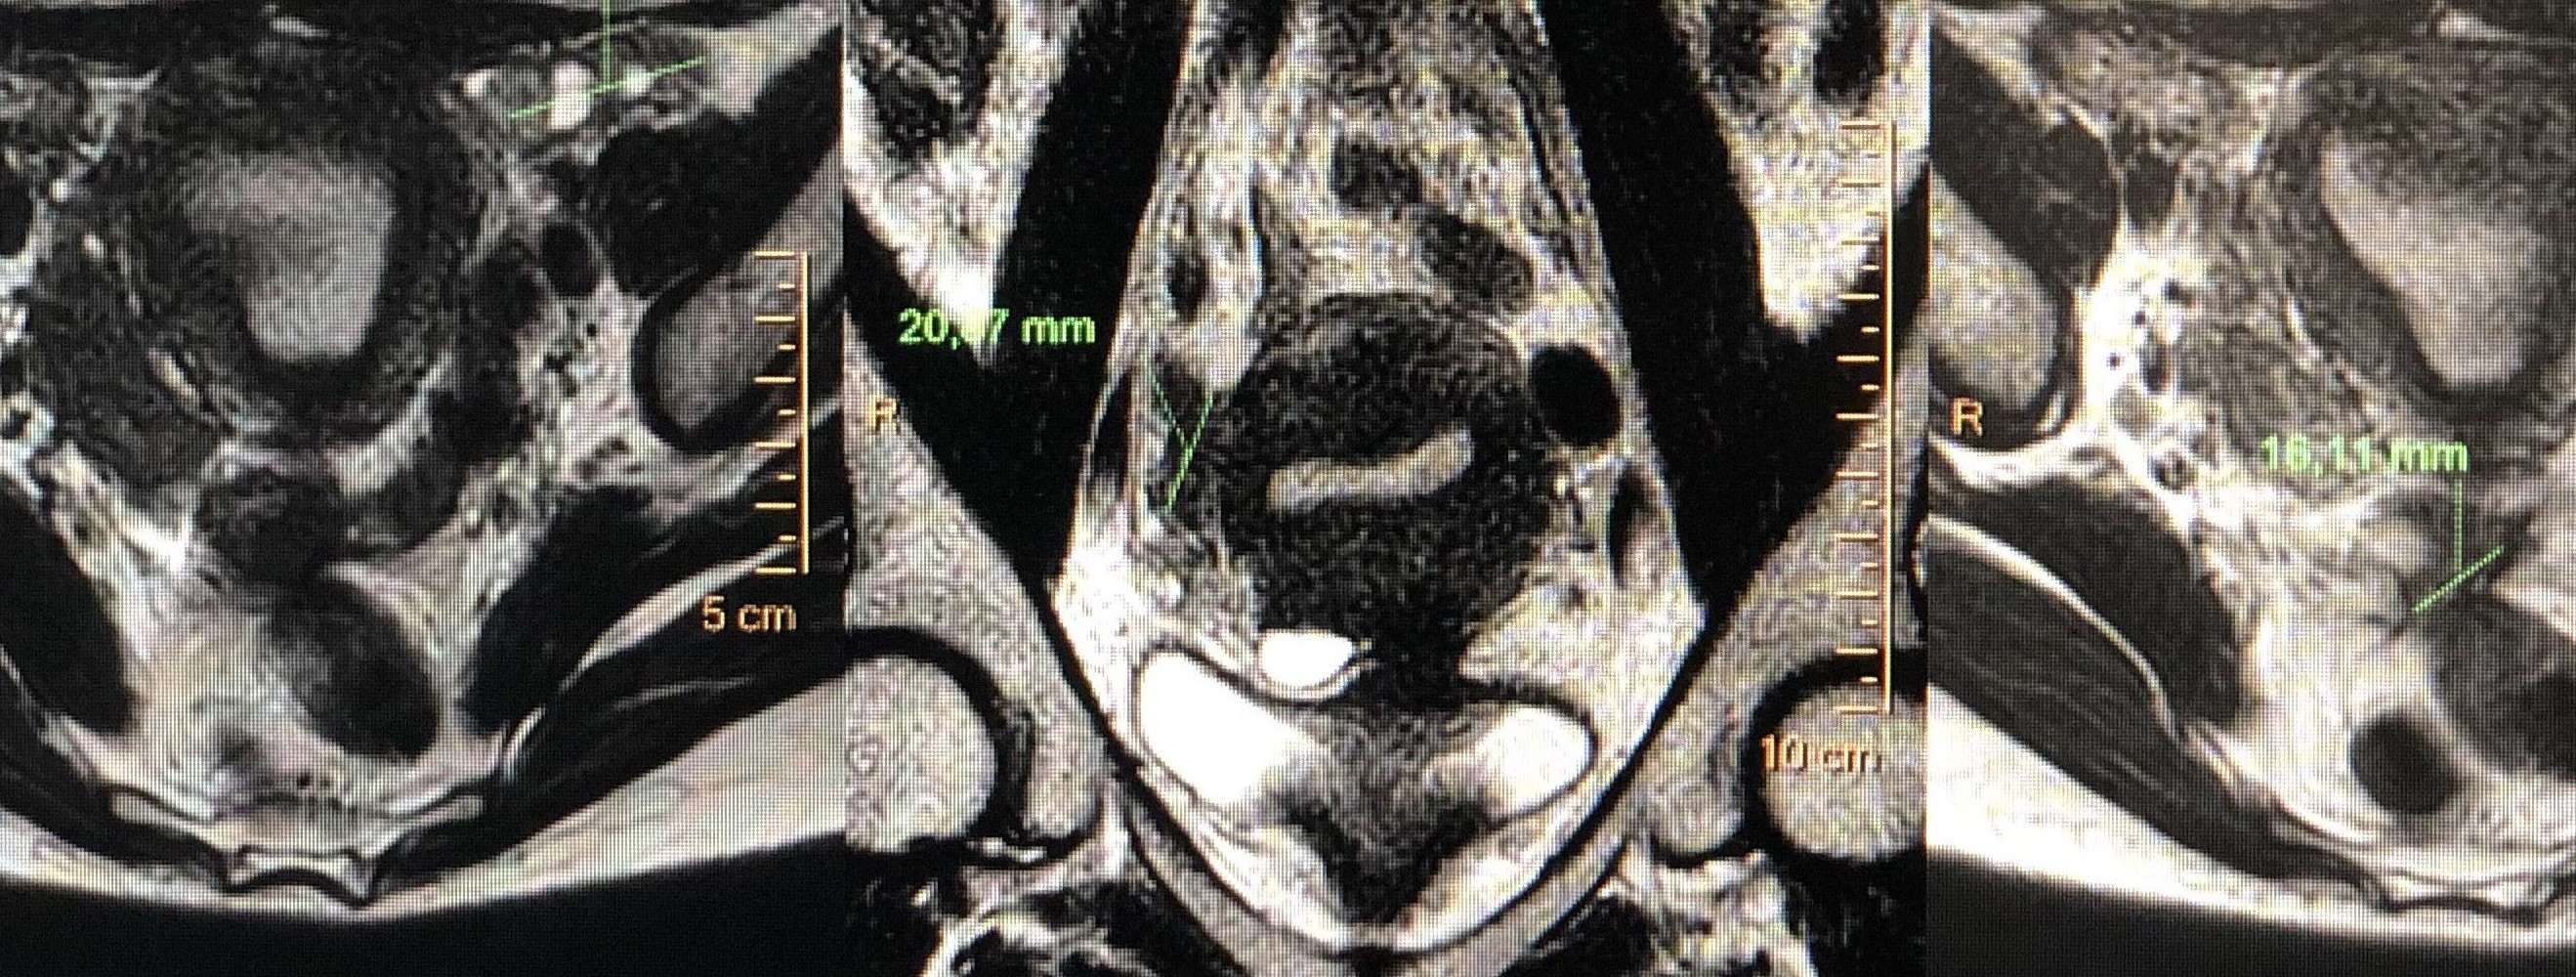

Schwanome du nerf crural gauche au contact du psoas

Adénome de la prostate

Endométriose vésicale et profonde